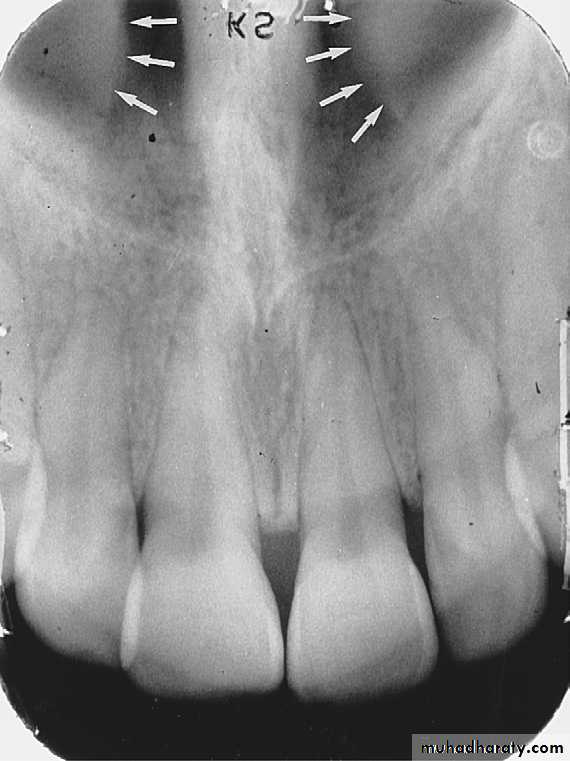

NASAL CAVITY: Is a pear-shaped compartment of bone located superior to the maxilla. On a maxillary perapical radiograph the nasal cavity appears as a large radiolucent area above the maxillary incisor.

NASAL SEPTUM:

The nasal septum is a vertical bony wall that divides the nasal cavity into right and left nasal fosse. Radiographically nasal septum appears as a vertical radiopaque partition that divide the nasal cavity.

ANTERIOR NASAL SPINE

: Is a sharp projection of the maxilla located at the anterior portion of nasal cavity. Radiographically the anterior nasal spin appears as a V shaped radiopaque area located at the intersection of the floor of nasal cavity and the nasal septum.

Inferior Nasal Conchae

Inferior nasal conchae are plates of bone that extend from the lateral walls of the nasal cavity. Inferior nasal conchae are seen in the lower lateral portions of the nasal cavity.Radiographically, inferior nasal conchae appear as a diffuse radiopaque mass or projection within the nasal cavity